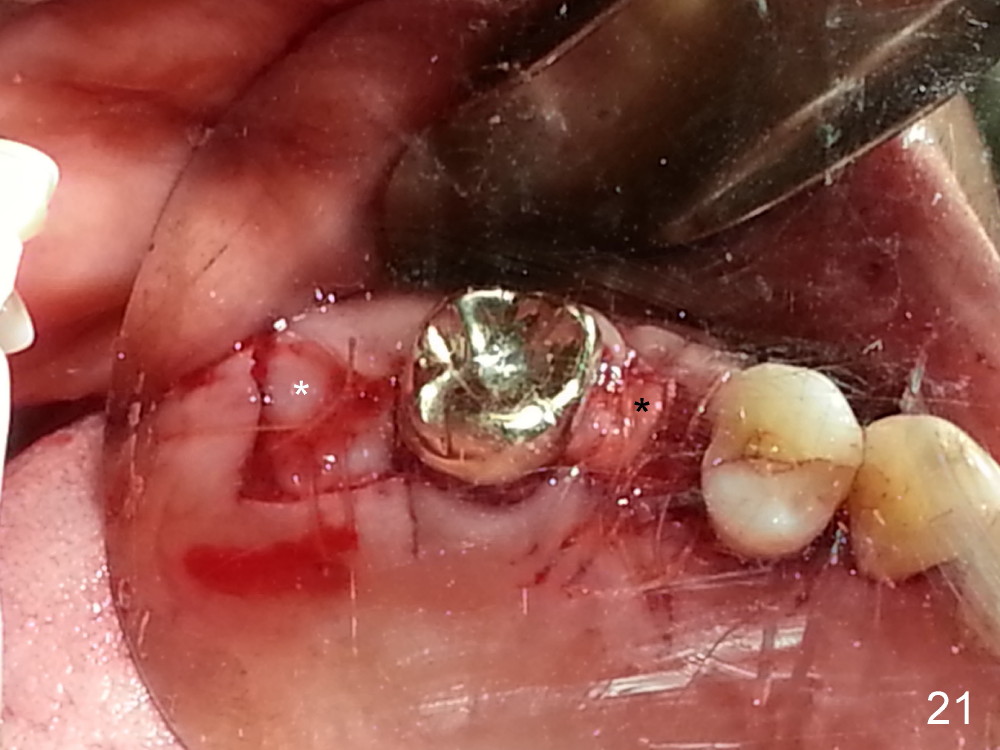

The tooth #13 appears to be affected by periodontits and occlusal trauma (Fig.1*). After using a periotome (Fig.2), the tooth is extracted (Fig.3). The buccal flap is raised (Fig.4). Gingival graft is to be harvested from the site of #15 (Fig.5). The tissue is elevated buccally (Fig.6) and separated (Fig.7). The donor site is covered by a collagen membrane (Fig.8*). A diamond bur is used to induce bleeding from the socket (Fig.9*). Osteotomy is initiated (Fig.10) and enlarged (Fig.11,12). A tapered implant is being placed (Fig.13-15) following internal sinus lift (Fig.16,17). The implant is placed subcrestally, followed by bone graft (Fig.18), soft tissue graft (Fig.19), and suturing (Fig.20 <, Fig.21).